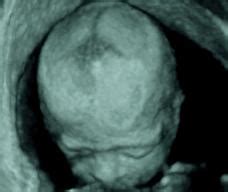

您好! 妊娠晚期影响羊水少于300ML者称为羊水过少,发生率为0、4—4%。羊水过少严重影响围生儿预后,羊水量少于50M,围生儿死亡率高达88%,应该高度重视。 B超检查羊水指数小于80MM为可疑羊水过少,小于50MM诊断为羊水过少。 您的检查结果是56MM,在羊水过少边缘,要引起重视。医生让您住院观察是有道理的,主要是为了胎儿安全。 您已怀孕38周多了,预产期提前或推后二周以内都是正常的,也就是说38周后生下的孩子发育已成熟,可以算是足月产的。 您现在感觉胎动频繁,有可能是胎儿缺氧的表现,建议您按医生要求住院。您在住院期间医生会加强观察,如果胎儿情况有变化,医生可以及时采取措施处理或提前结束分娩,以保证您和孩子的安全。 10月怀胎不容易,安全第一位,您说是吗? 祝您和宝宝健康!

妊娠晚期羊水量少于300ml者,称为羊水过少(oligohydramnios)。妊娠早、中期的羊水过少,多以流产告终。羊水过少时,羊水呈粘稠、混浊、暗绿色。过去认为羊水过少的发生率约为0.1%,但近年由于B型超声的广泛应用,羊水过少的检出率为0.5%~4%,发生率有所增加。羊水过少严重影响围生儿的预后而受到重视。 【病因学】 由于羊水生成及循环机制尚未完全阐明,有不少羊水过少的病例原因不明,临床多见下列情况。 1.胎儿畸形 如胎儿先天性肾缺如、肾发育不全、输尿管或尿道狭窄等畸形致尿少或无尿而引起羊水过少。 2.过期妊娠 过期妊娠时,胎盘功能减退,灌注量不足,胎儿脱水,导致羊水少。也有学者认为过期妊娠时,胎儿过度成熟,其肾小管对抗利尿激素的敏感性增高,尿量少导致羊水过少。由过期妊娠导致羊水过少的发生率达20%~30%。 3.胎儿宫内发育迟缓(IUGR) 羊水过少是胎儿宫内发育迟缓的特征之一,慢性缺氧引起胎儿血液循环重分配,主要供应脑和心脏,而肾血流量下降,胎尿生成减少而致羊水过少。 4.羊膜病变 电镜观察发现羊膜上皮层在羊水过少时变薄,上皮细胞萎缩,微绒毛短粗,尖端肿胀,数目少,有鳞状上皮化生现象,细胞中粗面内织网及高尔基复合体也减少,上皮细胞和基底膜之间桥粒和半桥粒减少。认为有些原因不明的羊水过少可能与羊膜本身病变有关。 【临床表现】 孕妇于胎动时常感腹痛,检查发现腹围、宫高均较同期妊娠者小,子宫敏感性高,轻微刺激即可引起宫缩,临产后阵痛剧烈,宫缩多不协调,宫口扩张缓慢,产程延长。若羊水过少发生在妊娠早期,胎膜可与胎体粘连,造成胎儿畸形,甚至肢体短缺。若发生在妊娠中、晚期,子宫四周的压力直接作用于胎儿,容易引起肌肉骨骼畸形,如斜颈、曲背、手足畸形。现已证实,妊娠时吸入少量羊水有助于胎肺的膨胀和发育,羊水过少可致肺发育不全。也有学者提出对过期妊娠、胎儿宫内发育迟缓、妊高征的孕妇,在正式临产前已有胎心变化,应考虑有羊水过少的可能。羊水过少容易发生胎儿窘迫与新生儿窒息,增加围生儿死亡率。上海统计围生儿死亡率,羊水过少者较正常妊娠高5倍。因此是重点防治的疾病之一。 【辅助检查】 B型超声诊断法 近年此法对羊水过少的诊断取得很大进展,但其诊断标准尚有不同意见。妊娠28周~40周期间,B超测定最大羊水池径线稳定在5.1±2.1cm范围,因此最大羊水池与子宫轮廓相垂直深度测量法(AFD)≤2cm为羊水过少;≤1cm为严重羊水过少。近年提倡应用羊水指数法(AFI)。此法比AFD更敏感、更准确。以AFI≤8.0cm做为诊断羊水过少的临界值;以≤5.0cm做为诊断羊水过少的绝对值。除羊水池外,B超还发现羊水和胎儿交界面不清,胎盘胎儿面与胎体明显接触以及胎儿肢体挤压卷曲等。 羊水直接测量 破膜时以羊水少于300ml为诊断羊水过少的标准,其性质粘稠、混浊、暗绿色。另外,在羊膜表面常可见多个圆形或卵圆形结节,直径2~4mm,淡灰黄色,不透明,内含复层鳞状上皮细胞及胎脂。直接测量法最大缺点是不能早诊断。 【诊断】 根据临床表现及辅助检查可做出诊断。 【治疗措施】 羊水过少是胎儿危险的、极其重要的信号。若妊娠已足月,应尽快破膜引产,破膜后若羊水少且粘稠,有严重胎粪污染,同时出现胎儿窘迫,估计短时间内不能结束分娩,在除外胎儿畸形后,应选择剖宫产结束分娩。剖宫产比阴道分娩可明显降低围生儿死亡率。 近年来应用羊膜腔输液防治妊娠中晚期羊水过少取得良好效果。方法之一是产时羊膜腔安放测压导管及头皮电极监护胎儿,将37℃的0.85%盐水,以每分钟15~20ml的速度灌入羊膜腔,一直滴至胎心率变异减速消失,或AFI达到8cm。通常解除胎心变异减速约需输注生理盐水250ml(100~700ml)。若输注800ml变异减速不消失为失败。通过羊膜腔输液可解除脐带受压,使胎心变异减速率、胎粪排出率以及剖宫产率降低,提高新生儿成活率,是一种安全、经济、有效的方法,但多次羊膜腔输液有绒毛膜羊膜炎等并发症. 一、羊水过少的原因: 羊水指数少於五公分,则称为羊水过少。 一般而言,孕妇轻微烧时,胎儿因有羊水的中介缓冲,并不会受到太大影响。张景文医师指出,孕妇发烧值得注意的是:其原因为何,如果只是感冒所引起的较无大碍;如果是感染疾病如德国麻疹、水痘,尤其是愈接近预产期的时候,对胎儿的不良影响愈大。孕妇体温持续过高超过38oC以上,使得子宫、胎盘血流量减少,宝宝会变得安少动。 (一)泌尿系统缺损: 与羊水过多相反,羊水过多是进水有问题,羊水过少则是排水有问题,泌尿系统出状况了,如输尿管阻塞、肾脏发育不全或尿道阻塞等。 (二)早期破水: 羊水外漏,入不敷出,当然水少。 (三)子宫胎盘血流不足: 任何造成子宫胎盘血流不足的情况,都会使羊水过少,如母亲有妊娠高血压、子痫症或子痫前症,胎儿有先天畸形等;血液供应不够,胎儿血液循环出状况,小便量自然减少,羊水也随之减少。 (四)胎盘钙化: 本来胎盘钙化,有一定的时间性,但若提早发生,或发生程度过剧,则会影响到胎儿血液循环,自然羊水也就少了,比如母亲有罹患梅毒或妊娠高血压等,都较易产生这种并发症。另外,过期妊娠也会因胎盘的功能的老化,而造成羊水过少的情形。 (五)同卵双胞胎: 这个在前面已提过,一个可能羊水过多,劣势的一,方就羊水不足了。 (六)其他如先天性畸形或胎盘早期剥离等,也会造成羊水过少。 二、羊水过少的影响及预后 比较少,但其成因却是威胁母体生命安全的主角,如高血压、梅毒、胎盘早期剥离等,所以如果是因母亲的疾患导致羊水过少,那一定要严密追踪治疗母亲,保障母亲的安全。 对胎儿而言,若因先天性的畸形或泌尿系统问题而造成的羊水过少,则只能视其程度,决定中止妊娠或出生后再治疗。胎盘功能不良的胎儿常会合并生长迟滞,早期破水的胎儿则大都有感染或早产的问题,所以预后都不好。 胎儿即本来很正常,却因其他因素造成羊水过少,也会产生很多后遗症,它可能因为挤压而发生形变轻者,脸歪歪的,严重的, 胎儿窘迫,也是胎儿承受不了压力的表现之一。另外羊水过少的胎儿可能发生肺脏发育不全,理由可能是压迫或缺乏羊水的吸入,以致於肺泡无法正常的生长舒展。 三、治疗 羊水过少者,除了针对母亲疾病作治疗外,另外可由卧床休息、多喝水来增加母亲的血液循环,间接的子宫胎盘的循环也得以增加,而达到增加羊水的目的;还可以使用羊膜腔灌注法,直接增加羊水量。但是如果经讦估发现胎儿有感染之虞,或胎儿状况不佳,不再适合在子宫内居住的话,都应该立即把它生下来,作妥善的照顾。 羊水数是多少?在家里可以适量吸氧气,因为羊水少BB容易缺氧,可以多喝点汤水,但现在作用不是很大了,定期去医院做胎心监护,每天数胎动。我有两个朋友羊水 都少,当时是3,后来都是顺产的,现在BB都四五个月了。